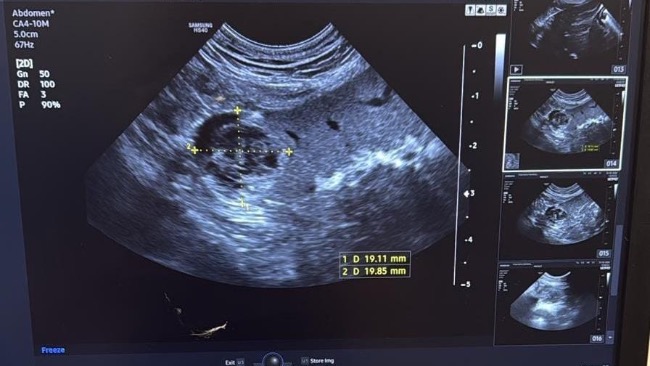

Podczas badania USG jamy brzusznej wykryto u niego guz na śledzionie. To nie jest „tylko” problem zdrowotny — to realne zagrożenie życia. Guz może w każdej chwili pęknąć i doprowadzić do krwotoku wewnętrznego.

Jedyną szansą dla Marleya jest pilna splenektomia – operacyjne usunięcie śledziony. Zabieg musi odbyć się w najbliższym czasie. Nie możemy czekać.